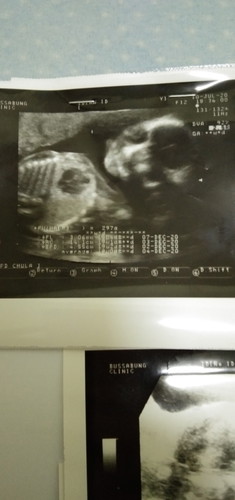

น้ำหนักเด็ก

ขอสอบถามแม่ๆหน่อยค่ะว่าใบชาวด์ของแม่บ้านอื่นมีบอกน้ำหนักกับความสูงของลูกไหมค่ะแม่ดูไม่ออกคะหมอไม่บอกความสูงและก็ไม่บอกว่าน้ำหนักเท่าไหร่บอกแต่ว่าน้ำหนักโอเคอยู่แม่ลืมถามคะแม่ๆลองทายดูค่ะว่าลูกชายหรือลูกสาวหมอบอกว่าลูกชายค่ะอิแม่ดูไม่ออกคะ